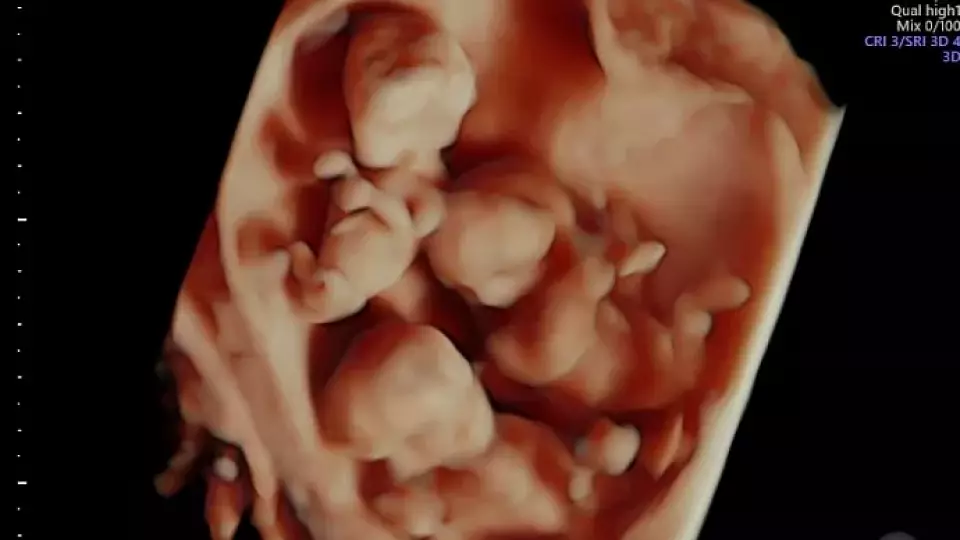

В Нижневартовске перинатальный центр внимательно следит за беременностью женщины, ожидающей тройняшек, которые будут очень похожи друг на друга.

Вероятность такой беременности составляет всего один случай на 200 миллионов. Это редкое явление известно как монохориальная триамниотическая тройня.

«Три плода имеют идентичные ДНК. Совместное существование трех плодов на одной плаценте ведущий фактор риска такой беременности. Но сегодня медицина шагнула далеко вперед, и врачи успешно справляются с ведением таких уникальных случаев, помогая женщинам обрести счастье материнства», – сообщили ugra-news.ru в пресс-службе департамента здравоохранения ХМАО.